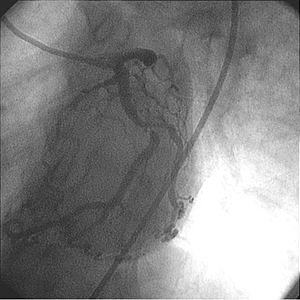

Sistema post ROTABLATOR

El equipo médico decidió usar el sistema Rotablator. Se atravesó la lesión con una oliva de 1,75 mm sin dificultad sobre la cuerda guía RotaWire™ Floppy.

• Luego de usar el sistema Rotablator™, se dilató la lesión con un balón para ACTP de 4,0 mm x 20 mm.

• El uso del sistema Rotablator™ facilitó el implante y la expansión adecuada de un stent de 4,0 mm × 9,0 mm con buen aspecto angiográfico.

Comentario del médico

El sistema Rotablator™ modificó la resistencia de la lesión y posteriormente facilitó el implante y la correcta expansión del stent mostrando con claridad su aplicación.

La evaluación angiográfica no reveló la presencia de calcio en la lesión.

Después de varios intentos por dilatar la lesión con balones, el nivel y la magnitud de la calcificación fue evidente. Si bien la oliva de 1,75 mm no aumentó el tamaño de la luz, sí permitió la posterior expansión de la lesión por medio de un balón y un stent para ACTP.